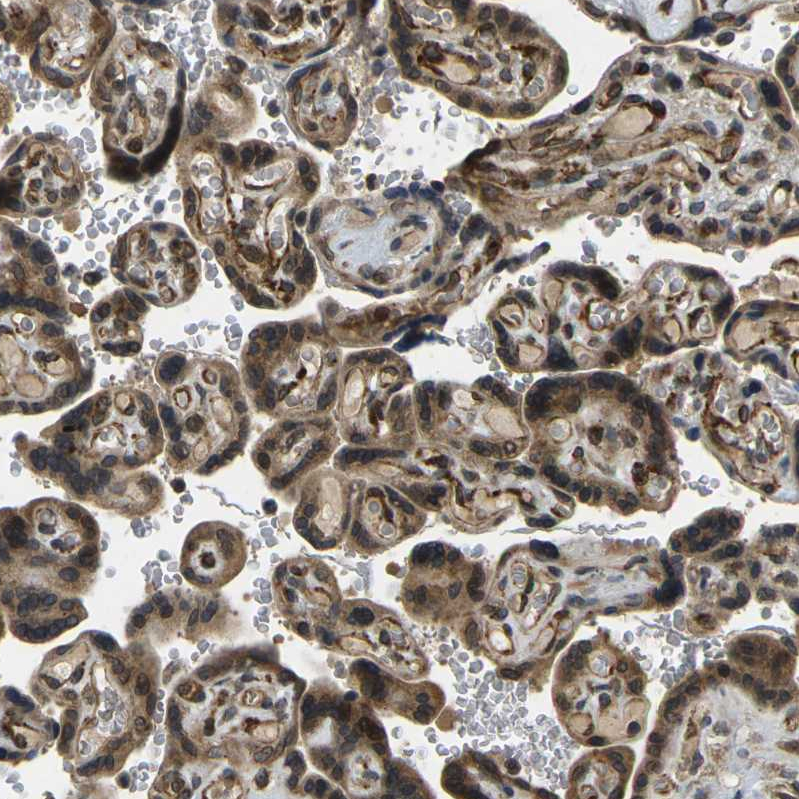

Immunohistochemical staining of human testis shows strong cytoplasmic membranous positivity in cells in seminiferous ducts and leydig cells.